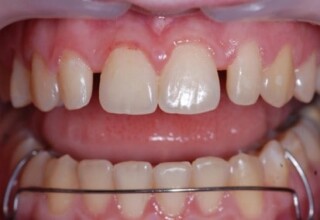

Οι όψεις ρητίνης προσφέρουν έναν οικονομικό τρόπο αισθητικής βελτίωσης της εμφάνισης των προσθίων δοντιών ενίοτε και των προγομφίων. Οι δυνατότητες τους πολλές, μπορούν να κάνουν και θαύματα! Ο μονός περιορισμός η κλινική ευχέρεια και η φαντασία του επεμβαίνοντος. Σε αυτήν την ασθενή οι τέσσερεις άνω τομείς είχαν ο καθένας το δικό του πρόβλημα(δυσχρωμία, απόκλιση) και επιπλέον: διαστήματα, πολλαπλές αποχρώσεις, κακή σχέση μεταξύ τους και με τα ούλα. Αποκαταστάθηκαν με τέσσερεις άμεσες όψεις ρητίνης (η μια πάνω σε στεφάνη πορσελάνης εμφυτεύματος!!!) οι οποίες κατασκευάστηκαν ενδοστοματικά!